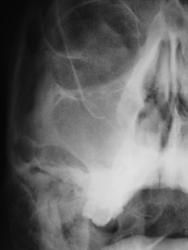

- https://radiomed.ru/sites/default/files/styles/case_slider_image/public/user/12/8.p.pc140012a.jpg?itok=_mUaMA2W

Правосторонний гайморит и фронтит с тотальным снижением пневмотизации правой гайморовой и правой половины лобной пазух; в левой гайморовой пазухе - вероятно киста в альвеолярной бухте; пристеночное снижение воздушности левой половины лобной пазухи.

+1. Но в левой лобной "кругляшка" больше на остеомку тянет.

Правосторонний гайморит, этмоидит, фронтит. Слева киста в/челстной пазухи.

Кругляшок слева в лобной похож на остеому.